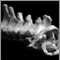

The cervical spine is part of the spine that runs through the neck area. It consists of seven vertebrae and eight pairs of spinal nerves (called C1 to C8). The two most common problems people have with the cervical spine are herniation and stenosis.